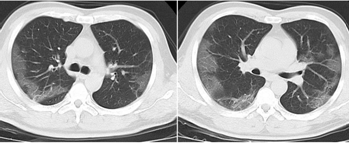

3.胸部影像學(xué)表現(xiàn)

早期呈現(xiàn)多發(fā)小斑片影及間質(zhì)改變,以肺外帶明顯。進(jìn)而發(fā)展為雙肺多發(fā)磨玻璃影、浸潤影,嚴(yán)重者可出現(xiàn)肺實變,胸腔積液少見。

外周散在多發(fā)小斑片影

支氣管、血管束增粗

雙肺多發(fā)GGO